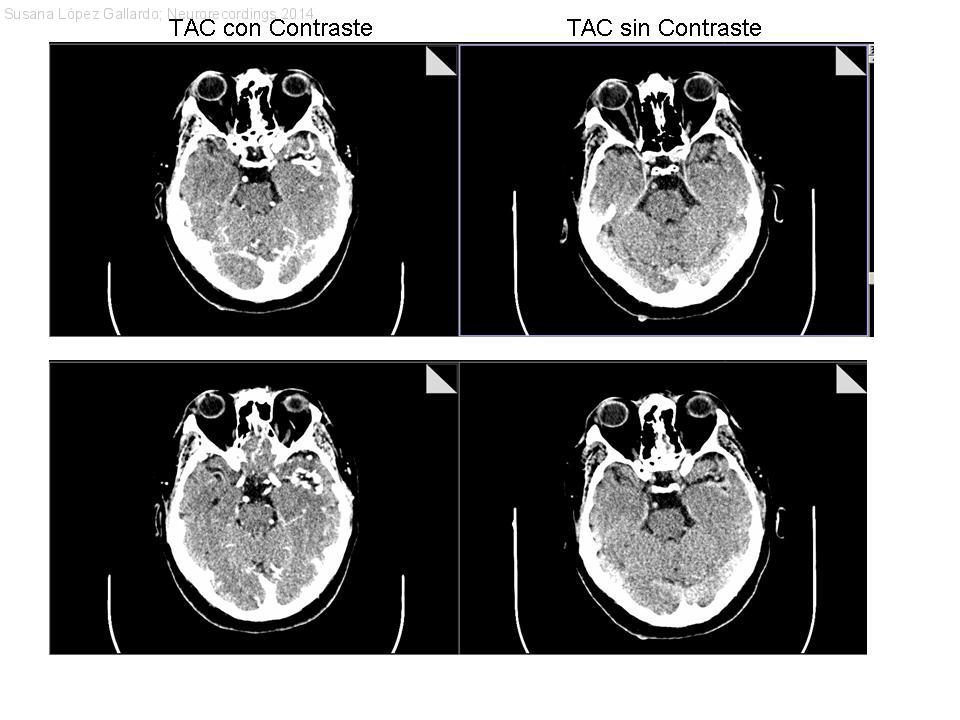

Epilepsia lesional, malformación vascular.

Diagnóstico final: Malformación Arterio Venosa

Neurología: Epilepsia | Patología cerebrovascular

Etiología: Malformación vascular